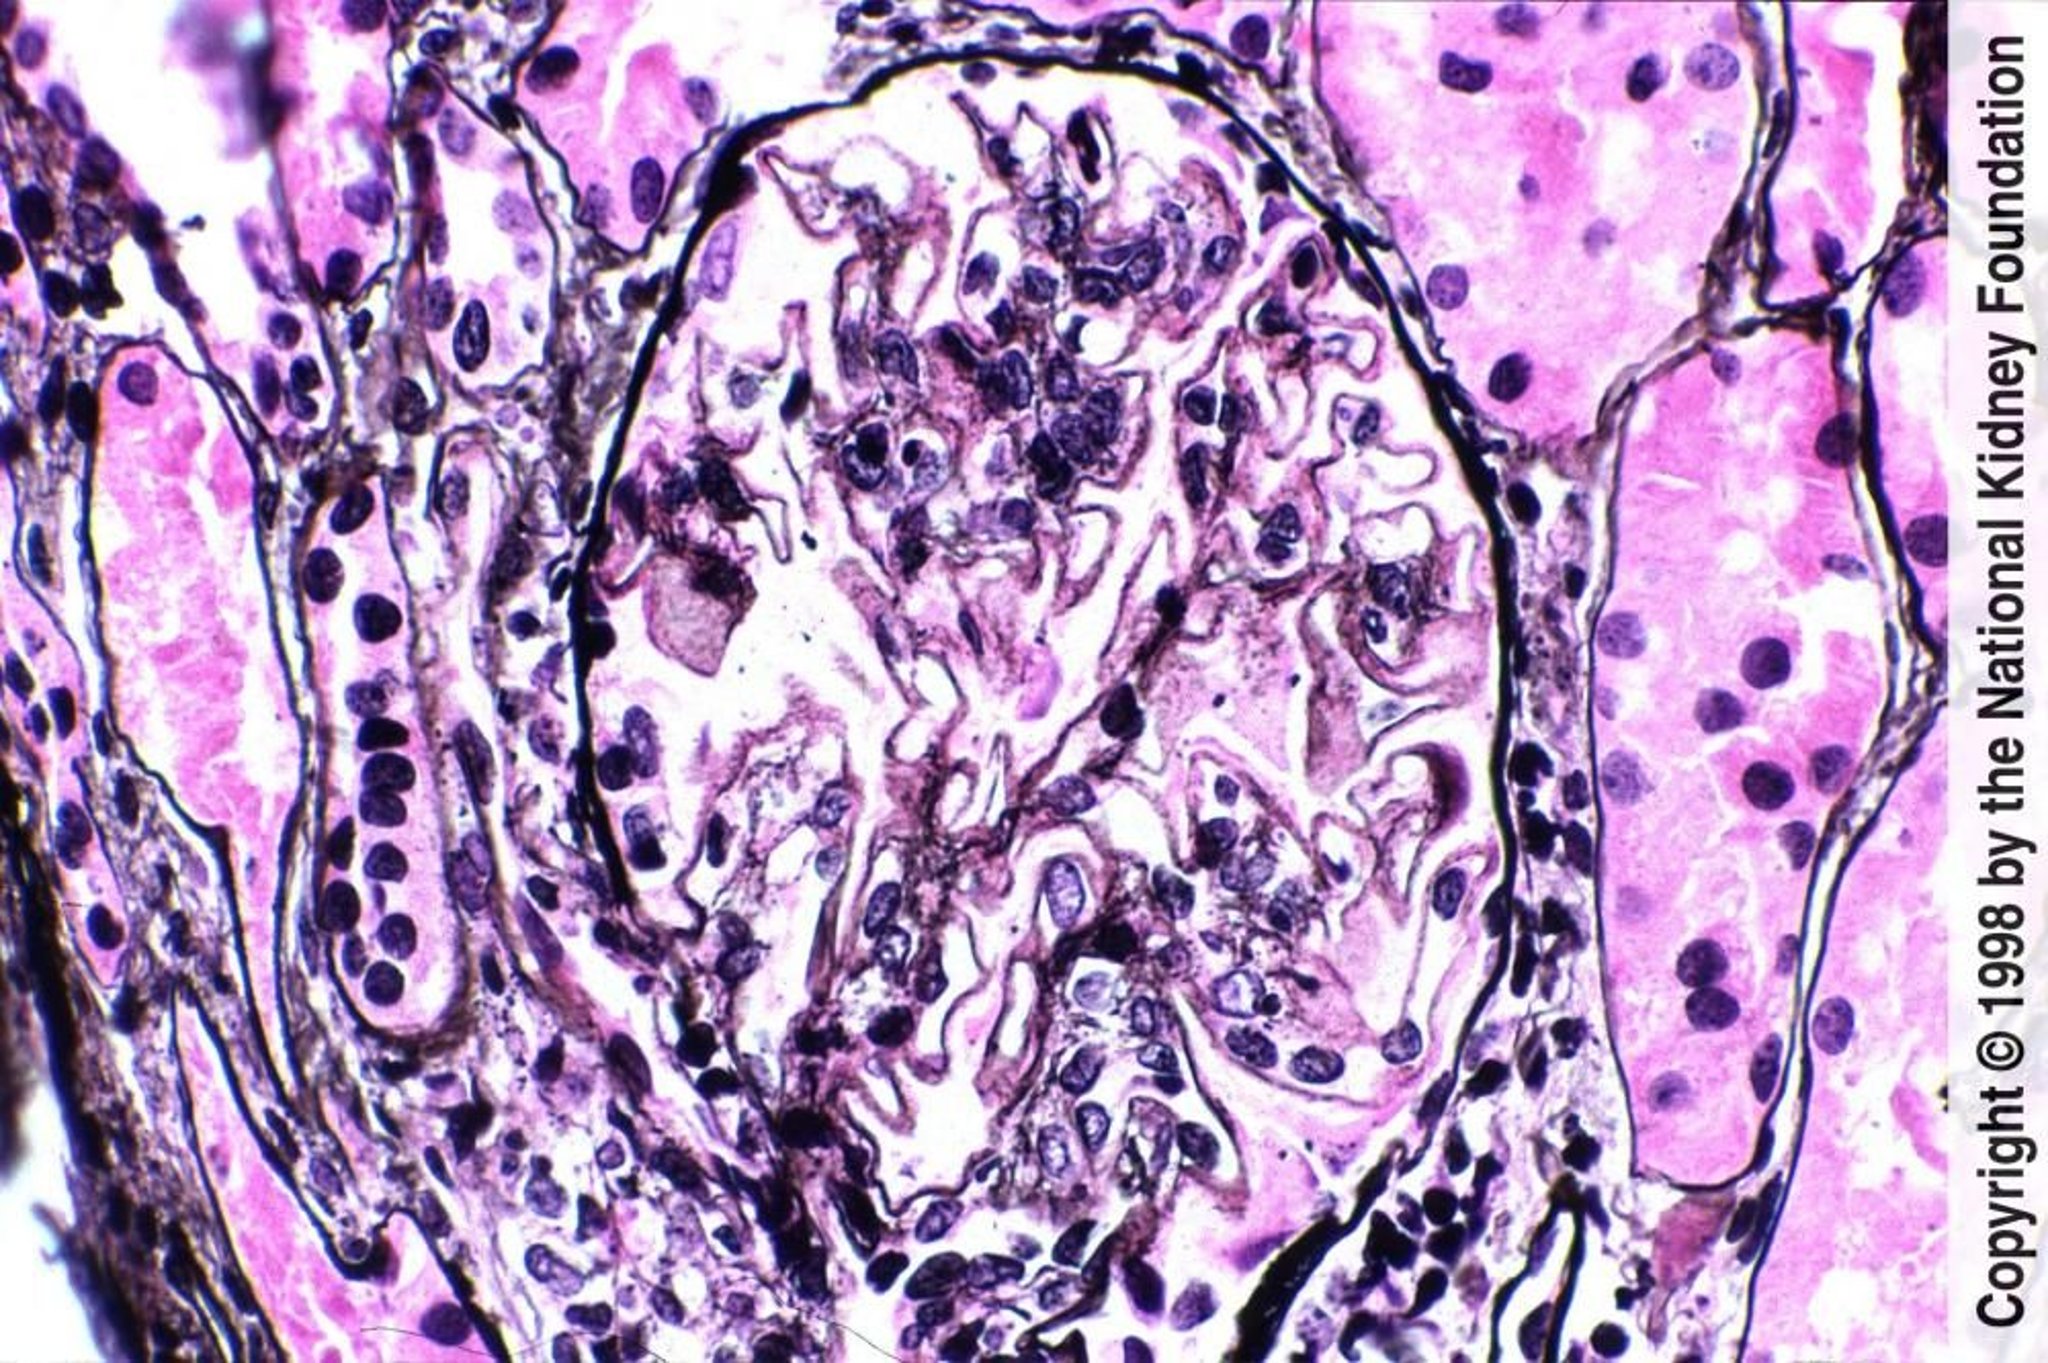

Nefritis lúpica: membranosa (clase V)

La presencia generalizada de soluciones de continuidad, las espigas pequeñas y la expansión mesangial leve con pequeñas áreas de coloración rosada indican depósitos mesangiales de complejos inmunes (tinción de plata de Jones, ×400).